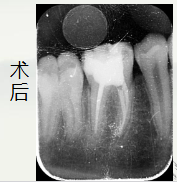

这里使用的是

松风纳米树脂 beautifil II A2色树脂

术后讨论:

牙冠修复:根管治疗后的牙齿失去牙髓营养供应,容易变脆。建议完成治疗

后做牙冠保护,但由于孩子还在生长发育,牙弓和颌骨可能会变化。我们可

能会先做一个预成冠(不锈钢牙冠)来暂时保护牙齿,它坚固耐用且经济。

等到孩子成年(18岁以后),颌骨发育基本稳定,再考虑更换为更美观的全

瓷冠或烤瓷冠。